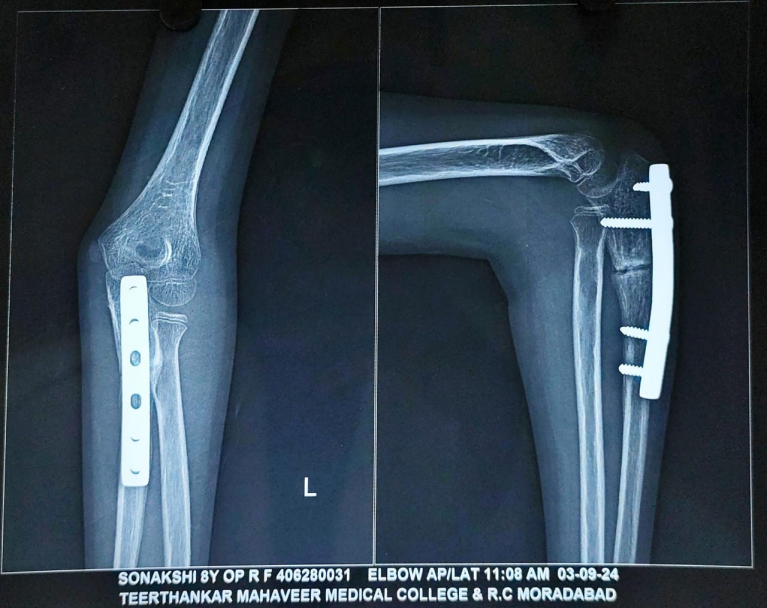

By the 9-month follow-up, radiographs confirmed complete union of the osteotomized ulna, and the radial head remained in a reduced, anatomical position. To prevent any implant-related complications, implant removal was done at 9 months (Fig. 8).

At the time of the past follow-up at 15 months, the X-ray demonstrated a well-maintained reduction of the radial head with congruent radiocapitellar alignment. The ulna showed complete union with satisfactory remodeling. There was no evidence of implant-related complications, re-dislocation, or deformity (Fig. 9). The child had regained a full, pain-free range of motion in the left elbow, including full flexion, extension, pronation, and supination (Fig. 10a, b, c, d). There were no signs of instability or functional limitations in daily activities. Almost complete recovery of PIN palsy was obtained. At the 15-month follow-up, physeal growth disturbance and angular deformities were evaluated and not observed. The patient achieved an excellent outcome as per the Mayo Elbow performance score.

Figure 9: Follow-up radiograph at 15 months after surgery. The image shows maintained reduction of the radial head with congruent radiocapitellar alignment, complete union and remodelling of the ulna, and absence of implant-related complications or re-dislocation.